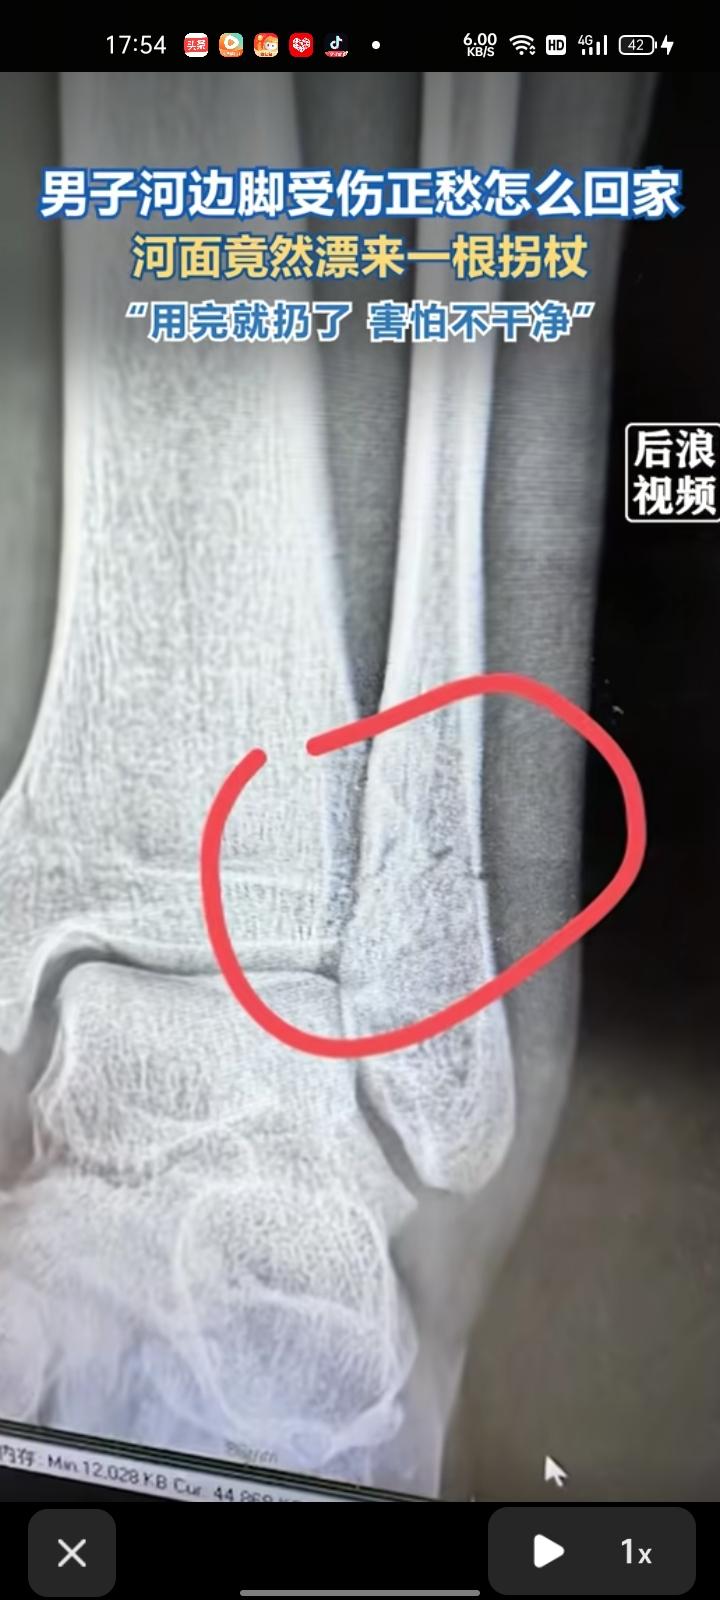

3月11日,四川成都。男子发视频表示,自己在河边被石头砸到脚导致骨折,正愁着怎么